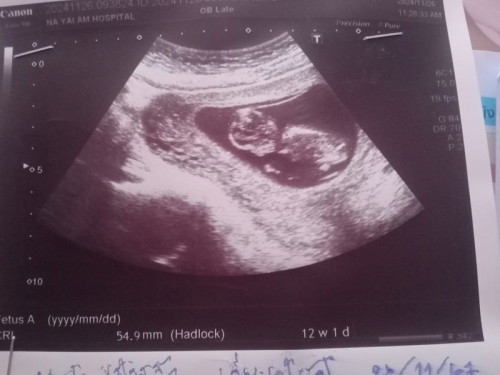

ซาวตอน12สัปดาห์

หมอไม่บอกอะไรเลยช่วยดูให้หน่อยค่ะว่านำ้หนักน้องเท่าไรตอนนี่เรา14+4วันแล้วค่ะนำ้หนักแต่ละบ้านเท่าไรกันแล้วค่ะ